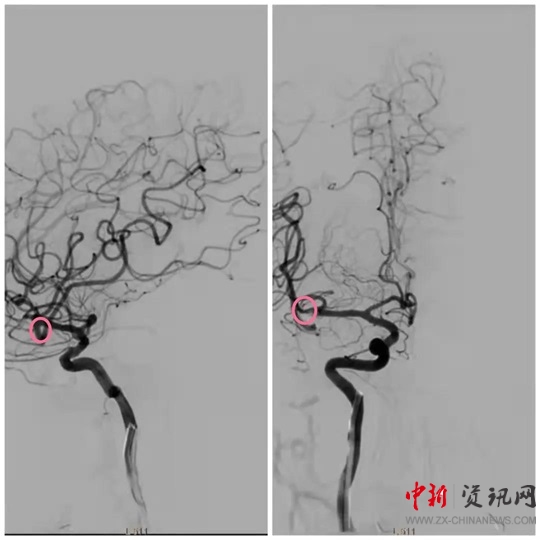

經(jīng)過一系列的術(shù)前準(zhǔn)備并經(jīng)患者家屬同意后,立即繞行病房進(jìn)入介入手術(shù)室,實(shí)施緊急手術(shù)。卒中中心團(tuán)隊(duì)、胸痛中心團(tuán)隊(duì)和介入團(tuán)隊(duì)密切配合,為患者分別實(shí)施了腦動脈造影+主動脈弓造影+顱內(nèi)動脈瘤栓塞術(shù)+冠狀動脈造影術(shù)+經(jīng)皮冠狀動脈支架植入術(shù),成功把患者從死亡邊緣拉回。目前,患者病情穩(wěn)定,各項(xiàng)指標(biāo)良好。

(動脈瘤栓塞前)

(動脈瘤栓塞后)